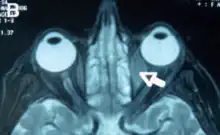

Orbital lymphoma

Orbital lymphoma is a common type of non-Hodgkin lymphoma that occurs near or on the eye. Common symptoms include decreased vision and uveitis. Orbital lymphoma can be diagnosed via a biopsy of the eye and is usually treated with radiotherapy or in combination with chemotherapy.